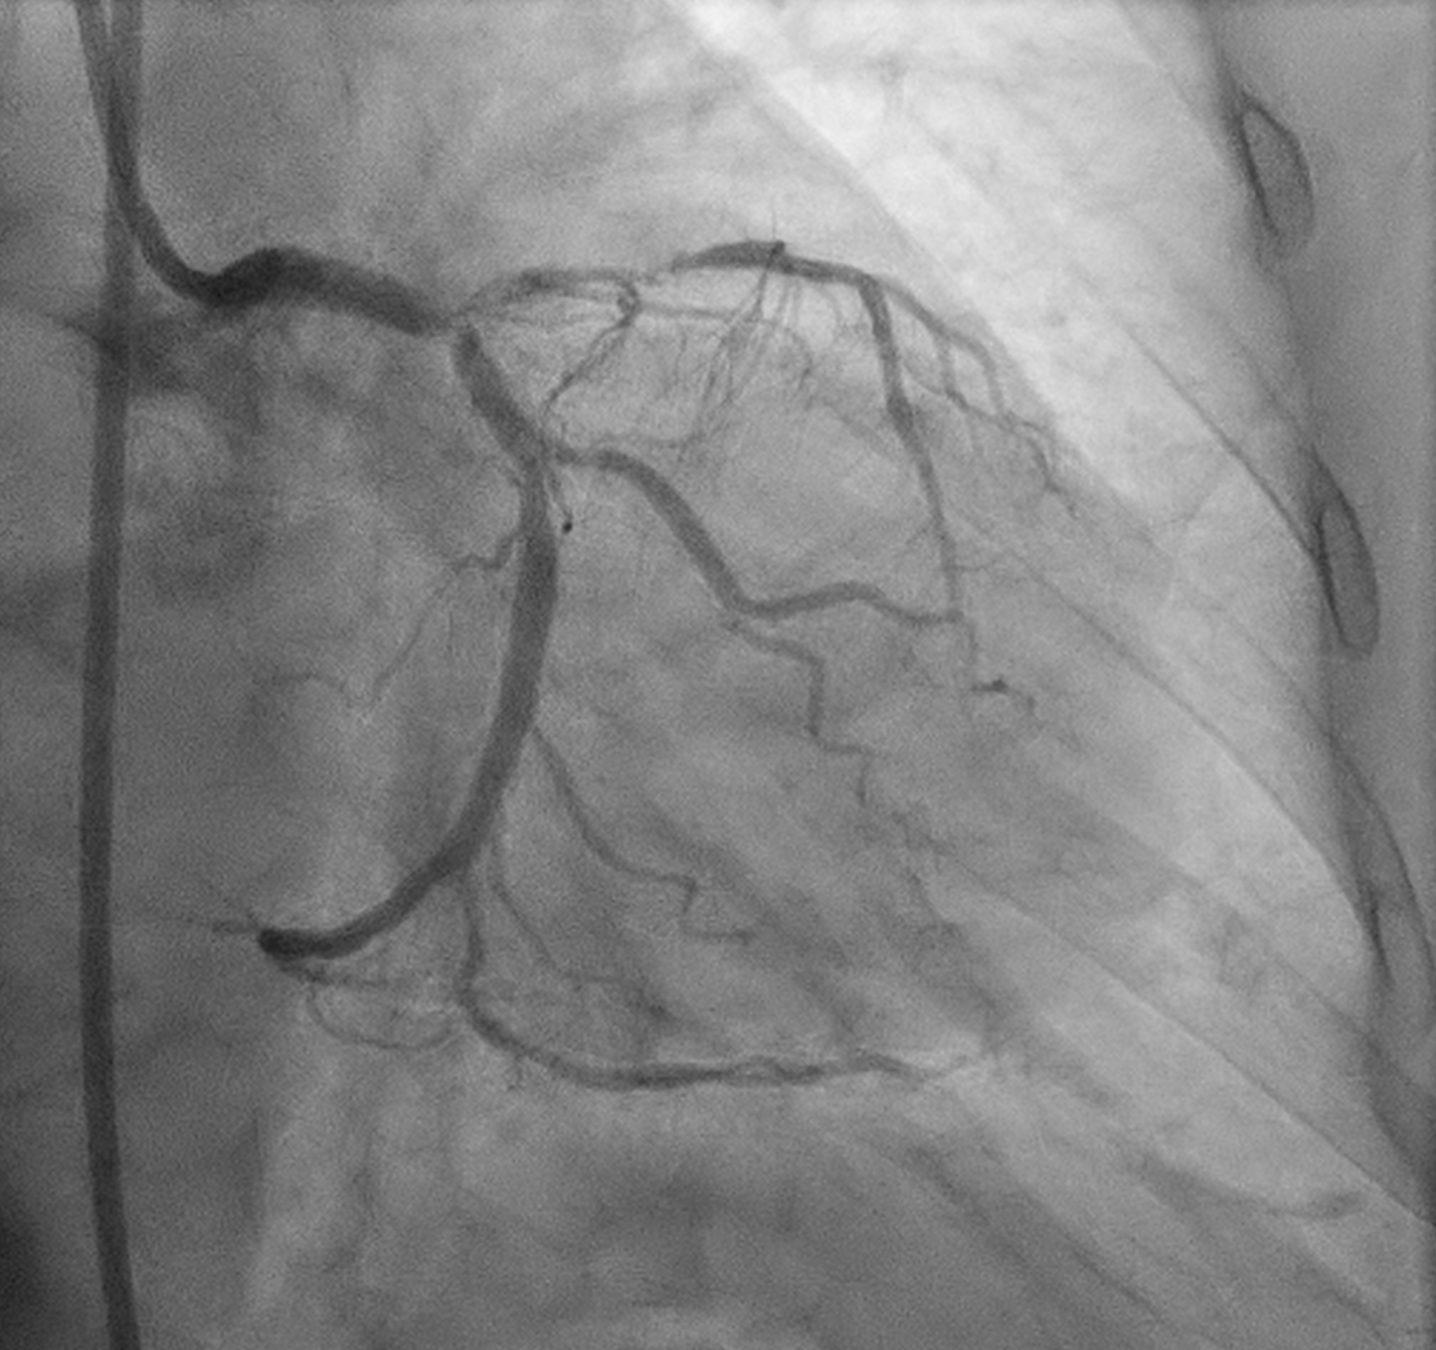

Angiography showed small non-dominant RCA with proximal severe stenosis, Left Main with severe tubular calcified stenosis at distal segmen, bifurcation lesion (medina1-1-1), LAD with diffuse calcified subtotal stenosis from ostial–mid, and LCX iwth severe tubular calcified stenosis at ostial.

PCI was initiated with Full Dose Heparin. LAD wired with Runthrough NS Floppy; predilatation with 2.0 ¡¿ 15 mm SC balloon. IVUS failed to cross proximal LAD, showing nodular calcium. Rotational atherectomy was performed using Rotapro 1.75 mm burr (180,000 rpm, four runs) followed by one polishing run at 150,000 rpm. Chest pain and ST elevation occurred shortly after rotablation due to Type F dissection in distal LM (TIMI 0 LAD). Bailout stenting with Promus Premier 3.5 ¡¿ 38 mm from LM–LAD was performed using jailed-balloon technique, followed by post-dilatation and IVUS optimization.